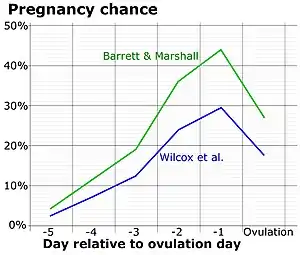

Predicting ovulation

The detection of a surge in release of luteinizing hormone indicates impending ovulation. LH can be detected by urinary ovulation predictor kits (OPK, also LH-kit) that are performed, typically daily, around the time ovulation may be expected.[31] A conversion from a negative to a positive reading would suggest that ovulation is about to occur within 24–48 hours, giving women two days to engage in sexual intercourse or artificial insemination with the intention of conceiving.[32]

As sperm can stay viable in the woman for several days, LH tests are not recommended for contraceptive practices, as the LH surge typically occurs after the beginning of the fertile window.